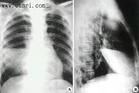

肺脓肿 肺脓肿: 肺组织由于化脓菌感染引起组织炎症坏死,继而形成肺脓肿,如与支气管相通,则出现脓腔。临床上以高热、咳嗽、咳大量臭脓痰为其特征。 因咯血入院检查初定肺脓肿,住院治疗青霉素类抗生素,注意休息,效果不好,建议再根据情况决定改何种药物。要定期复查。